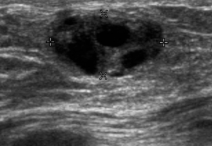

Identify this image.

Galactocele